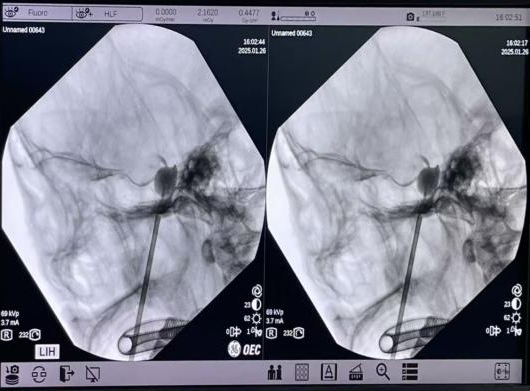

該手術是一種微創介入治療方法,在影像精準引導下,將球囊導管插入三叉神經半月節,然后注入造影劑使球囊膨脹,壓迫神經纖維,從而達到止痛的目的。

1月26日(小年夜前夕),陳龍主任醫師與陸維主治醫師在王文華主任醫師的指導下,為靳先生實施手術。術中影像顯示,球囊位置精準,創口僅為2毫米,手術過程順利。

▲術中穿刺

▲球囊釋放位置精準